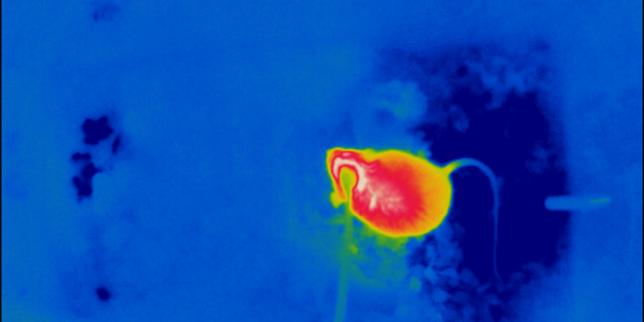

© Laboratoire de Markus H. Schmidt, docteur en médecine

Le chercheur croit que l’arrêt de ce type de recherche nuira au traitement des maladies cardiaques.